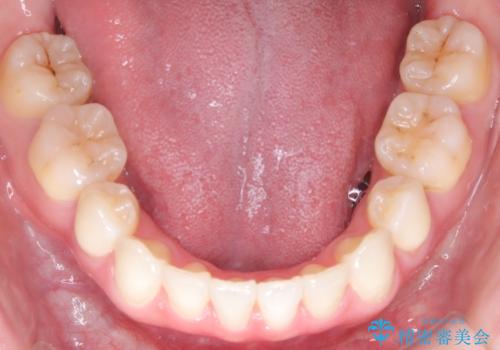

【抜歯インビザ】前歯の凸凹をなおしたい

- 前歯の凸凹を主訴に来院されました。

前歯はあまり下げる必要がなかったため、上下左右の第二小臼歯抜歯を行う治療計画としました。

途中、臼歯の近心傾斜を認めましたが、追加アライナーを使用することでリカバリーを行いながらインビザラインのみで治療を完了することができました。